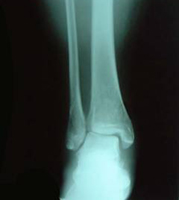

X線所見:脛骨は正面像で下端部の骨折が認められ、末梢骨片は後外方へ転位していた。中枢骨片は側面像で前下方への転位を認めた。腓骨は下端部で斜骨折を認めるが、転位は認めなかった。

初診時の写真・X線

スライドの写真は初診時の外観で内出血の様子

レントゲンの矢印が骨折線を示す